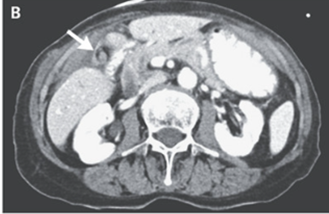

腹部CTでは外側壁肥厚を伴う腫大した胆嚢を認めた。

また胆嚢動脈および胆管の渦巻き所見を認めたが、総胆管の拡張は認めなかった。